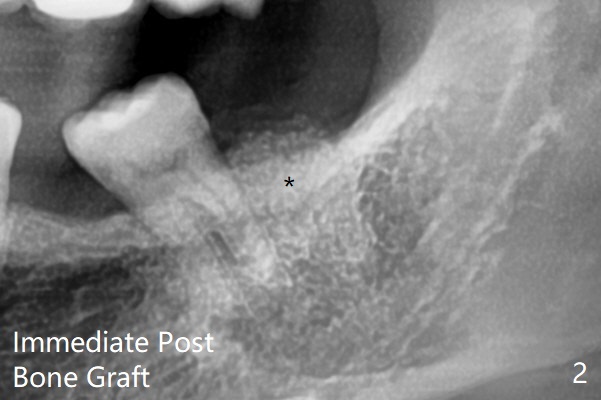

粘性骨粉植骨(图二:*)。术后一两个月(伤口愈合,18号牙牙冠远中面充分暴露)后,准备口扫做无形局部矫正(Clear Aligner),竖直18号牙。然后再口扫制作19号牙种植导板。